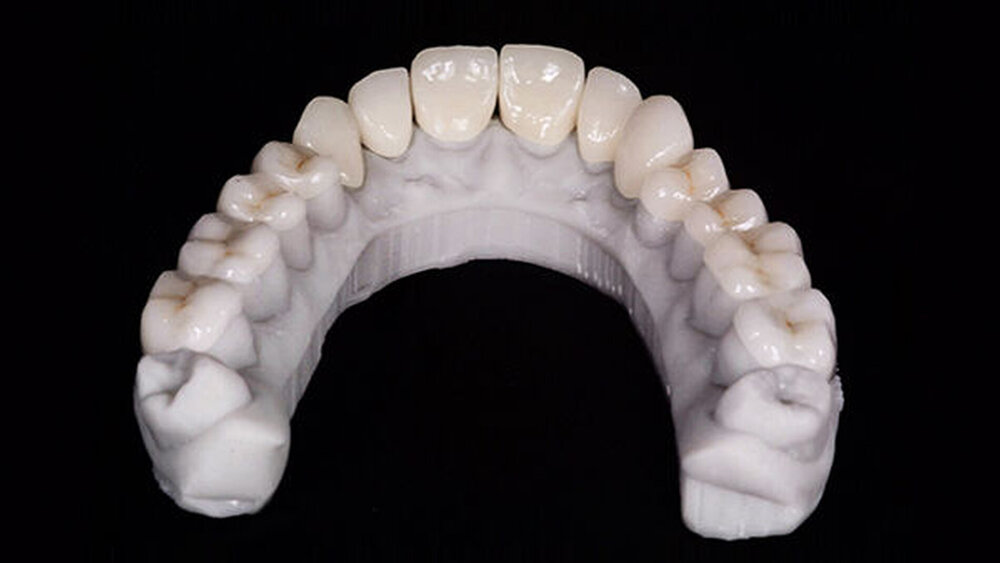

Die endgültigen Veneers und Kronen wurden mit der Konstruktionssoftware „Ceramill mind“ (Amann Girrbach) digital vorbereitet und in einer Fräsmaschine (Ceramill Motion 2, Amann Girrbach) aus maschinell bearbeitbaren Lithiumdisilikat-Keramikblöcken (VITA BLOCS TriLuxe forte für Ceramill Motion 2, Amann Girrbach) gefertigt (Abb. 10). Nach der Bestätigung des Randschlusses und der optischen Eigenschaften bei einem probeweisen Einsetzen wurde ein Lippen-Wangen-Halter (OptraGate, Ivoclar Vivadent) angelegt.

Die Kronen (11–13, 21–23) und Veneers (14, 15, 16, 17, 24, 25, 26, 27, 31, 32, 33, 34, 35, 36, 37, 41, 42, 43, 44, 45, 46, 47) wurden mit einem lichthärtenden, polymerisierenden Harz‧adhäsiv (Futurabond U und Bifix QM; VOCO) an den Abutments befestigt. Zur Polymerisation wurde ein Hochleistungs-LED-Lichthärtegerät verwendet (Celalux 3; VOCO), siehe die Abbildungen 11 und 12.